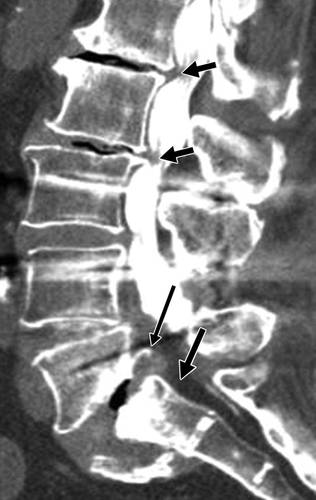

图11A-69岁女性,在L1后压缩性骨折手术后12个月进行随访。矢状CT图像显示L1椎体及内置物(箭头)。 原始L1椎体前部已完全吸收。 L1椎后部(箭头)的高度明显降低。

图11B-69岁女性,在L1后压缩性骨折手术后12个月进行随访。冠状CT显示内置物(箭头)的凹陷,现在它位于横向稳定螺钉的顶部。